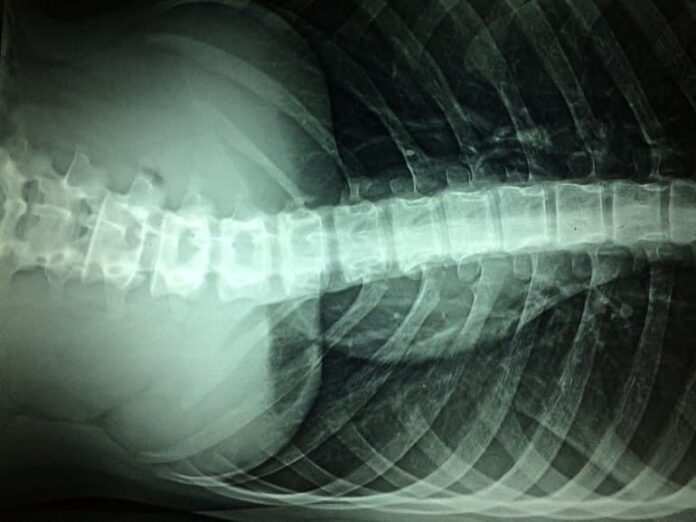

This is an xray of a spinal cord

Spinal cord injuries affect hundreds of thousands of people in the United States, with thousands more diagnosed each year. Image is in the public domain